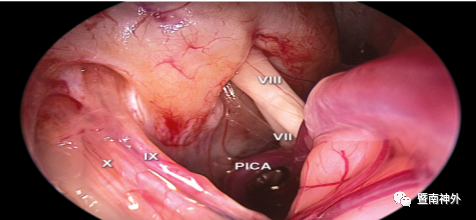

4.对于内听道前型CPA脑膜瘤,颅神经通常在肿瘤的后表面,需在颅神经的间隙中操作,并分块切除肿瘤。三叉神经是最能耐受推移的神经,需充分利用该神经上、下间隙作为手术通道,其他手术通道可选择CN VII/VIII复合体和后组颅神经之间的间隙。嵌入肿瘤内的颅神经和血管结构需小心保护,以免损伤;对于桥脑外侧缘需进行锐性分离,注意保护好桥脑腹侧表面的软脑膜及静脉,避免损伤脑干;

5.本例肿瘤长入’s囊腔、内听道口内,借助内镜或者反观镜小心分离其内与神经粘连紧密的肿瘤,避免损伤,实现了全切肿瘤及面、听神经功能保留的目标;

术中电生理监测:脑干、面听、三叉神经功能未见异常